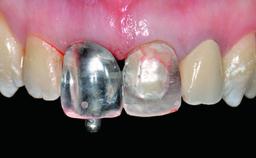

Type of Implants Reduced-Diameter|Two-Piece

Attachment Reduced-Diameter|Two-Piece

Prosthesis Type FDP

SAC Level Advanced

Defining Characteristics One missing tooth to be replaced by an implant-borne crown

Loading Protocol Conventional or early

Retention Screw-retained Screw-retained

Provisional Implant-Supported Prosthesis Prosthodontic margin > 3 mm apical to mucosal margin Prosthodontic margin > 3 mm apical to mucosal margin